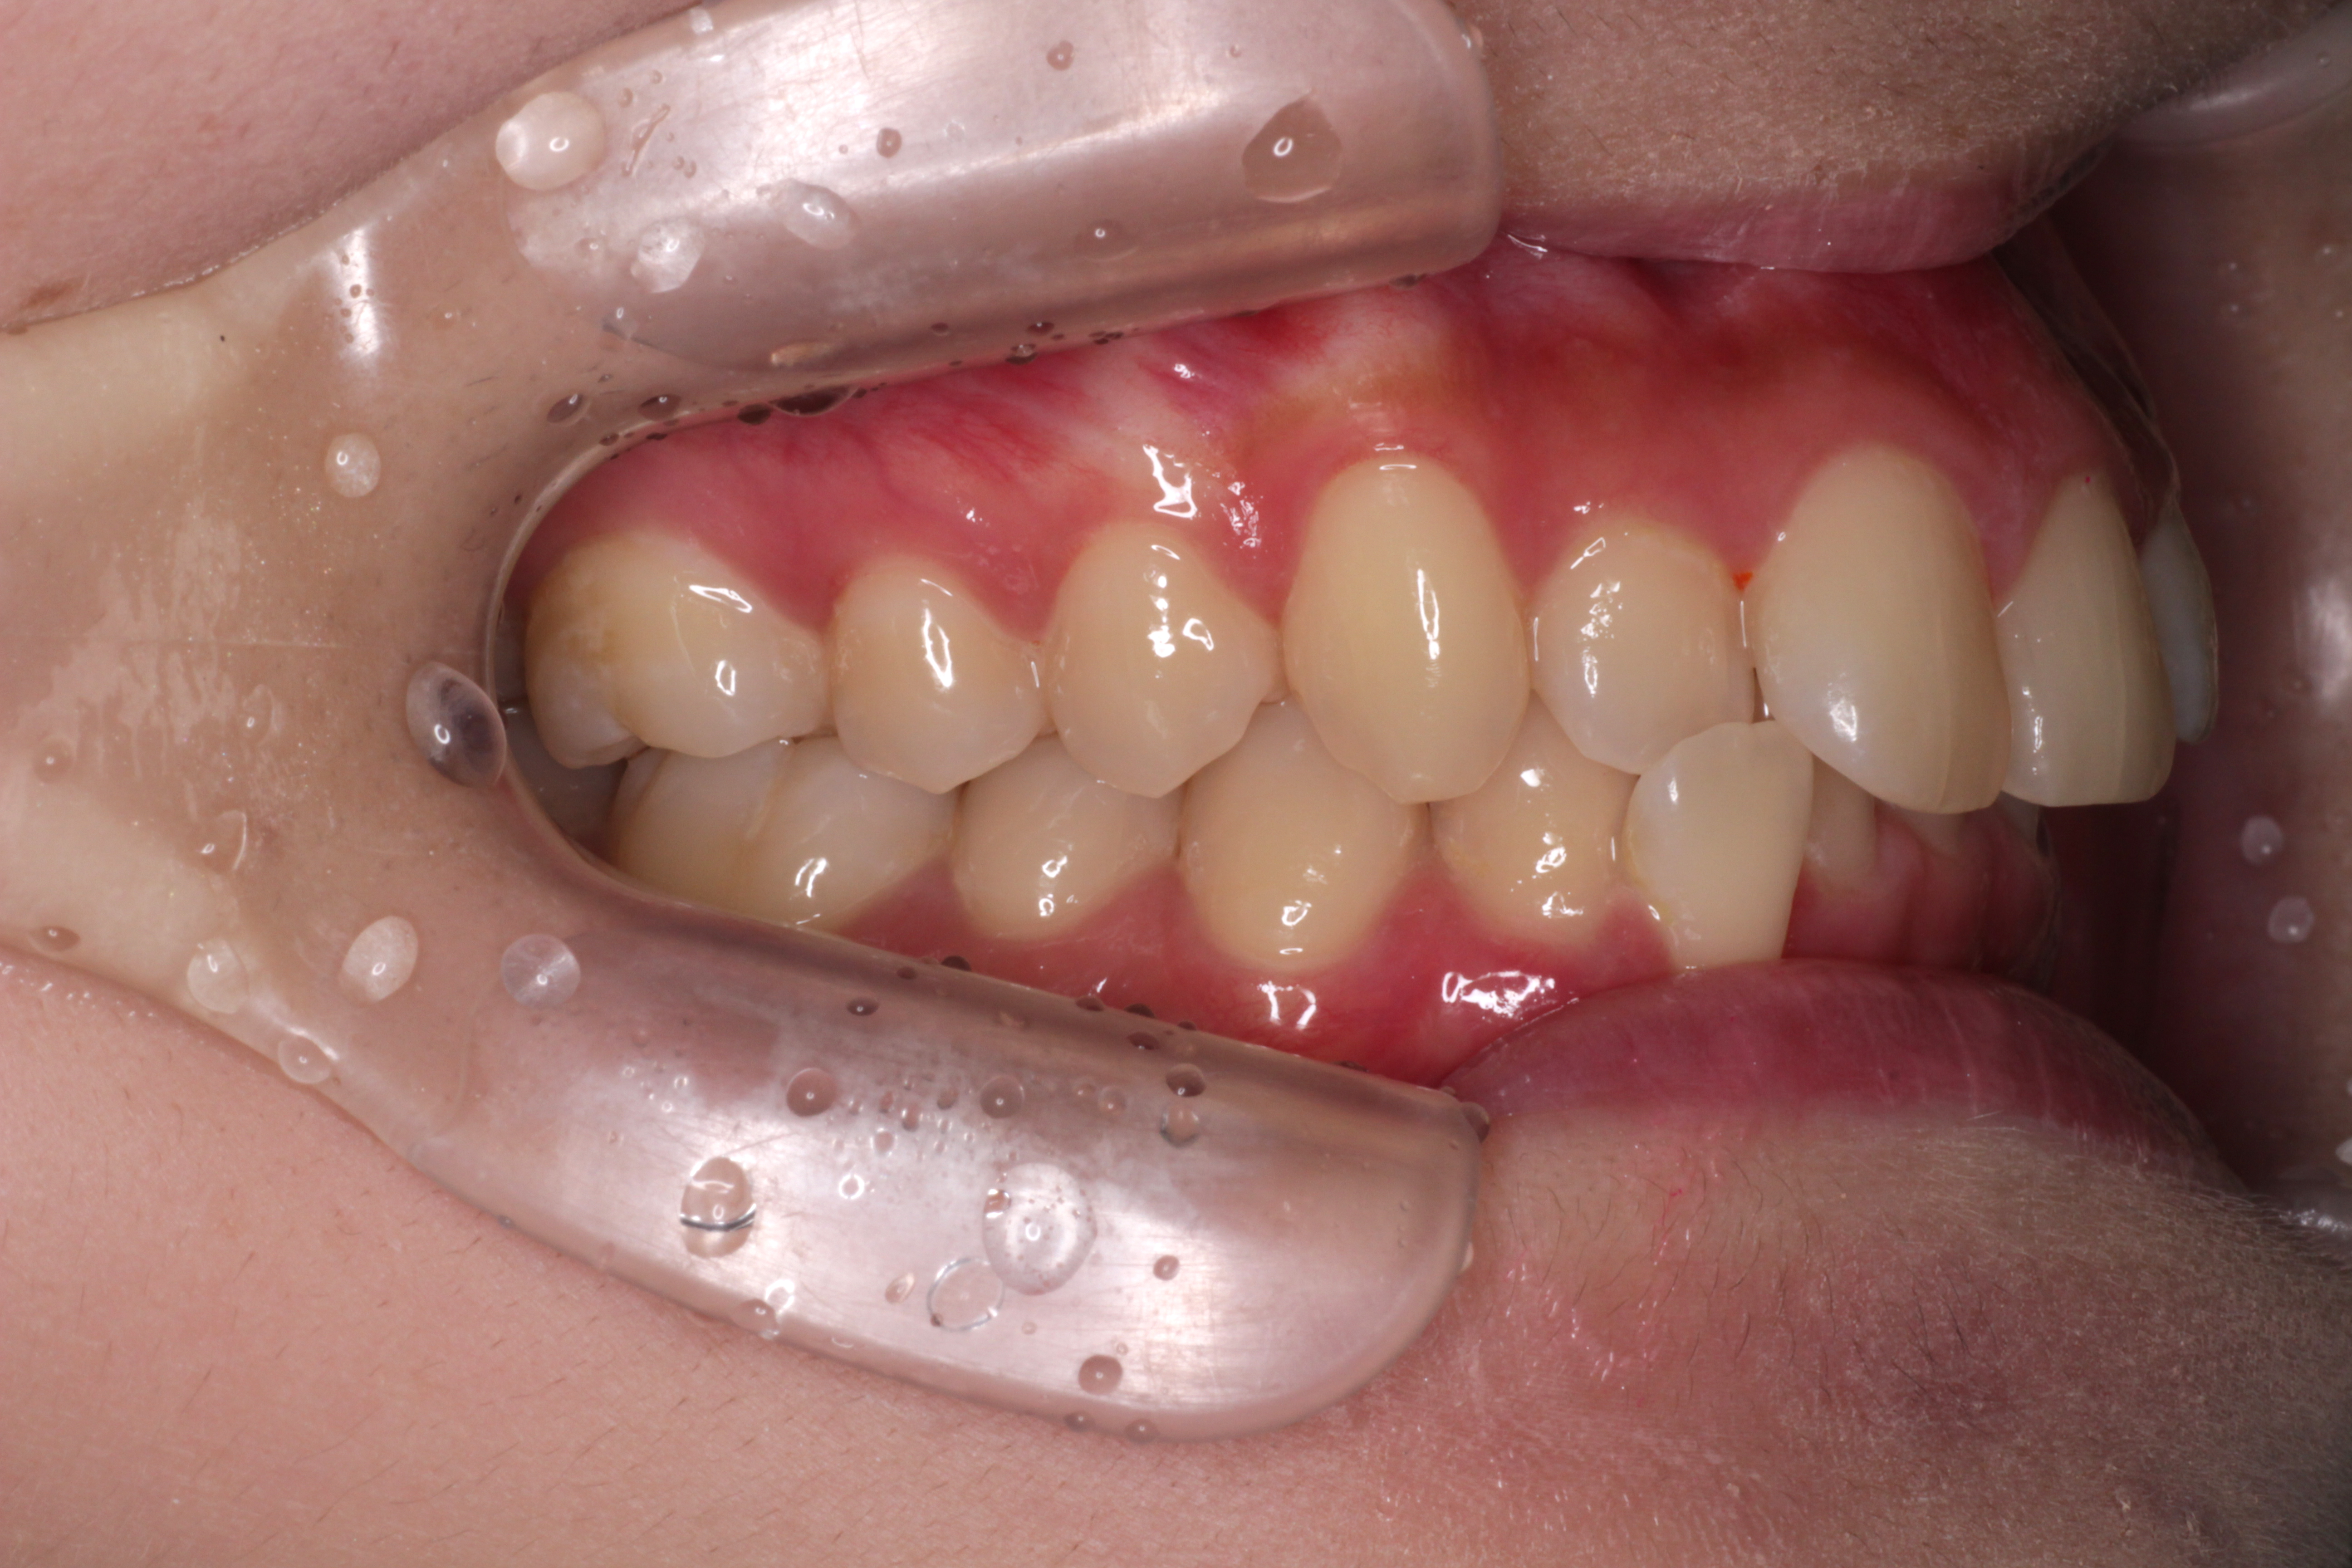

↓お口の中の状態です。

初診時からの変化と治すべきところは

⑴咬み合わせは下の歯が上の歯に隠れていましたが、見えるようになりました。

⑵右下の2番目の歯が歯列の中に納まってきましたが、まだ少しずれています。

⑶右上の2番目の歯は下の歯より前に出ましたが、咬み合わせが浅いです。

ここで新たな問題点が見つかりました。

⑷正中がずれているので、合わせるためにゴムかけをします。